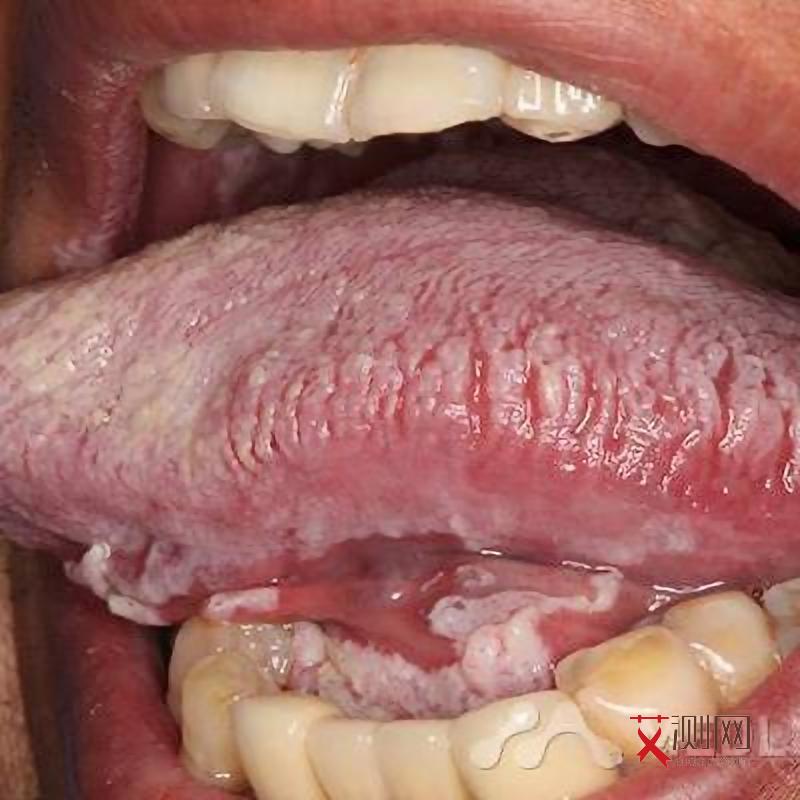

当免疫系统被严重破坏,CD4 + T淋巴细胞计数明显下降,感染者就会进入艾滋病期。此时,身体会出现各种严重的机会性感染和肿瘤,症状复杂多样且严重,如持续发热、盗汗、腹泻、体重急剧下降、各种严重的真菌感染、病毒感染、细菌感染,以及卡波西肉瘤、淋巴瘤等恶性肿瘤。艾滋病期的症状持续时间难以一概而论,如果不进行积极有效的抗病毒治疗,病情会不断恶化,症状会持续存在,严重影响生活质量和预期寿命。而如果及时接受规范的抗病毒治疗,症状可以得到一定程度的控制,生活质量也会有所提高,生存期也能得到延长。